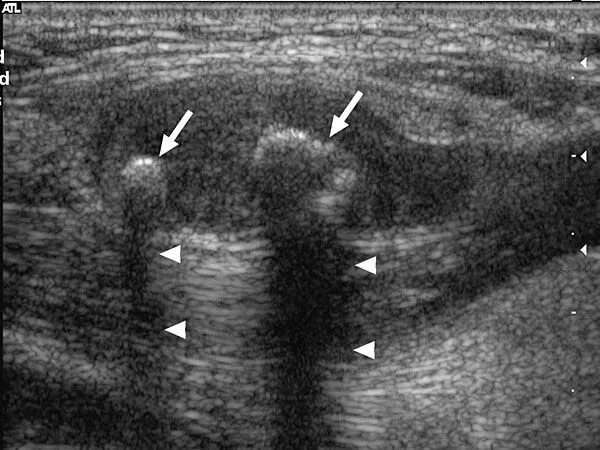

Метастазы в паховых лимфоузлах